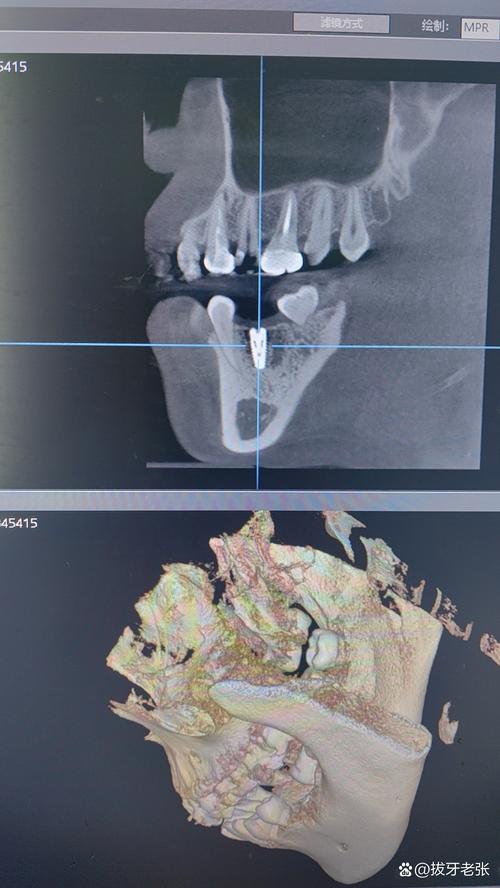

CBCT是通过锥形X线束围绕患者头部旋转扫描,通过计算机重建生成三维影像,具有以下特点:

- 三维可视化:可任意角度旋转、切割图像,直观显示牙槽骨的立体形态,精确测量骨高度、宽度、厚度(误差可控制在0.1mm以内);

- 高分辨率:能清晰分辨下颌神经管、上颌窦底、颏孔等重要解剖结构的位置、边界及与牙槽嵴的距离;

- 骨密度评估:通过CT值可量化骨密度(Hounsfield单位,HU),区分骨皮质(致密骨,HU>1000)和骨松质(疏松骨,HU=100-500),帮助选择合适的种植体(如骨密度低时选择表面粗糙的种植体以增强初期稳定性)。